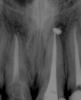

Ico Опубликовано 22 декабря, 2010 Поделиться Опубликовано 22 декабря, 2010 Для обработки каналов пользуюсь протейперами,для обтурации дают только стандартную и конусную гутту(04 и 06) и АН+.Плотно по объёму обтурировать иногда не получается-боюсь продавить силер,т.к. за пафы "ругают".Апексы стараюсь не ломать,силером только стенки обмазываю.Хочется ещё и дельту максимально закрыть.Знаю,что необходимо трёхмерное пломбирование,но пока вопрос о приобретении такой системы в клинику остаётся открытым.Доктора,посоветуйте,пожалуйста,как можно наиболие грамотно "залатералить" канал,разработаный протейпером?Попробуите сделать ап.упор фаилами и латеральте на здоровье.Апекс зондироавть только 10 - 15 а протеипер S2 ,F1 может апекс раскрыть поэтому доводите его на 1мм до апекса остальное делаите Н и К фаилами.Конусную гутту хорошо латералить не получится,она плотнее и под вертикалку нужна,кстати она и дороже обычнои гутты.Насчет пафов не знаю у меня они случаются иногда.семерка- до апексов на 0.5 фаил 30 дистальныи не помню но нобольше. http://s003.radikal.ru/i204/1012/c9/37316d43c891.jpgЗдесь мезиальные 30,дистальныи 35.http://i040.radikal.ru/1012/d4/c964ae3700cd.jpgПафы пошли 0,5 до апекса 45 фаил.http://s007.radikal.ru/i300/1012/b7/c1ae61d83293.jpgздесь 35 фаил.http://i045.radikal.ru/1012/11/05e37b25844e.jpghttp://i070.radikal.ru/1012/ac/e4cf942fa4a8.jpgПримерно так получается.Что дают тем работаем. Ссылка на комментарий

ger_berra Опубликовано 22 декабря, 2010 Автор Поделиться Опубликовано 22 декабря, 2010 Да МЕТА самая простоая и недорогаяПонятно.Есть такая.А мои снимки зацените,а то самооценочка хромает.Только,плиз,ничем не кидайтесь(тапками,помидорами,яйцами и т.п.),что без кофера.Каюсь,уже заказала набор.После 3-х недель с метапексом.Гранулирующий переодонтит 21Он же на метапексе.Прошло 3 месяца,постоянная обтурация АН+ гуттой(латералка) Ссылка на комментарий